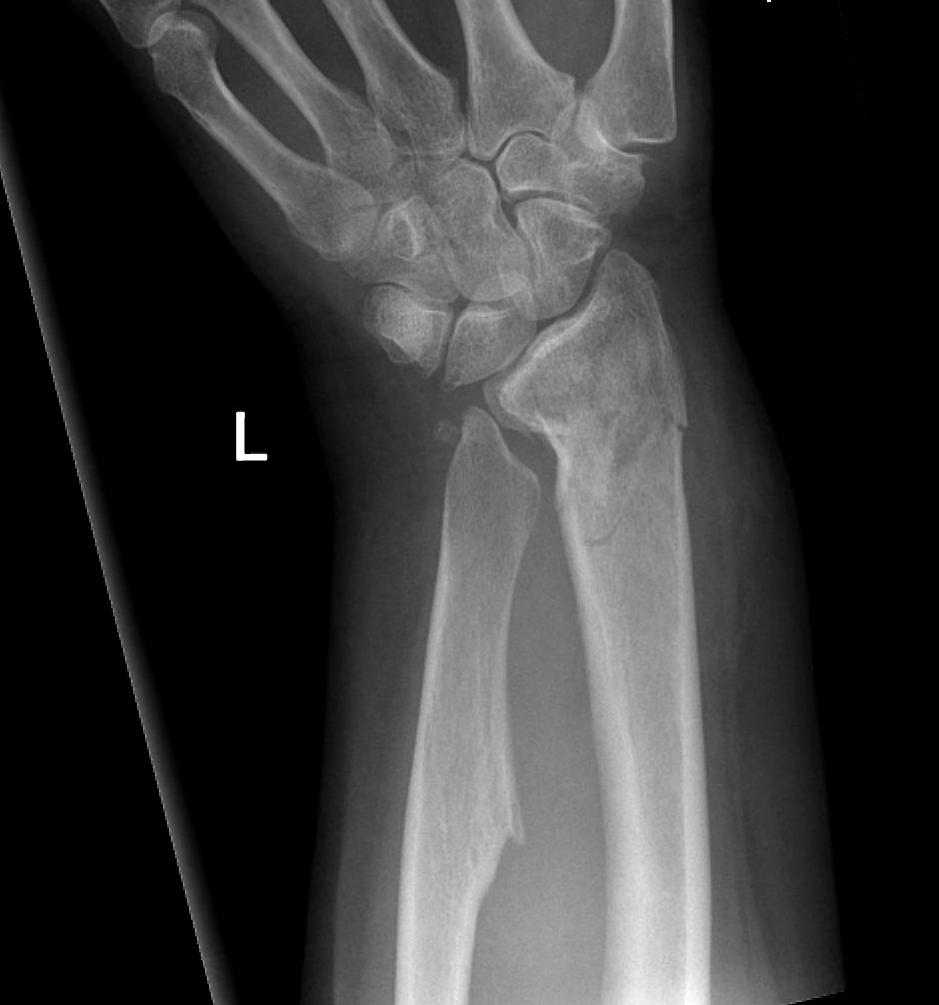

X-ray

Volar-ulna tilt of the distal radius with dorsal subluxation of ulna / distal radius triangular shape

Proximal carpal row becomes wedge shaped

- lunate "falls into" the radio-ulna gap

DRUJ widened